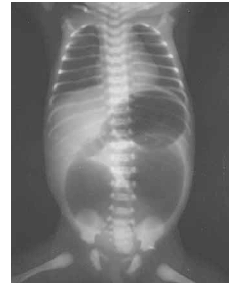

Considere que um neonato de 24 horas de vida apresenta vômitos biliosos. Considere ainda que a radiografia simples do tórax e abdome desse paciente tem o aspecto mostrado abaixo. Nesse caso, o diagnóstico mais provável é atresia duodenal.